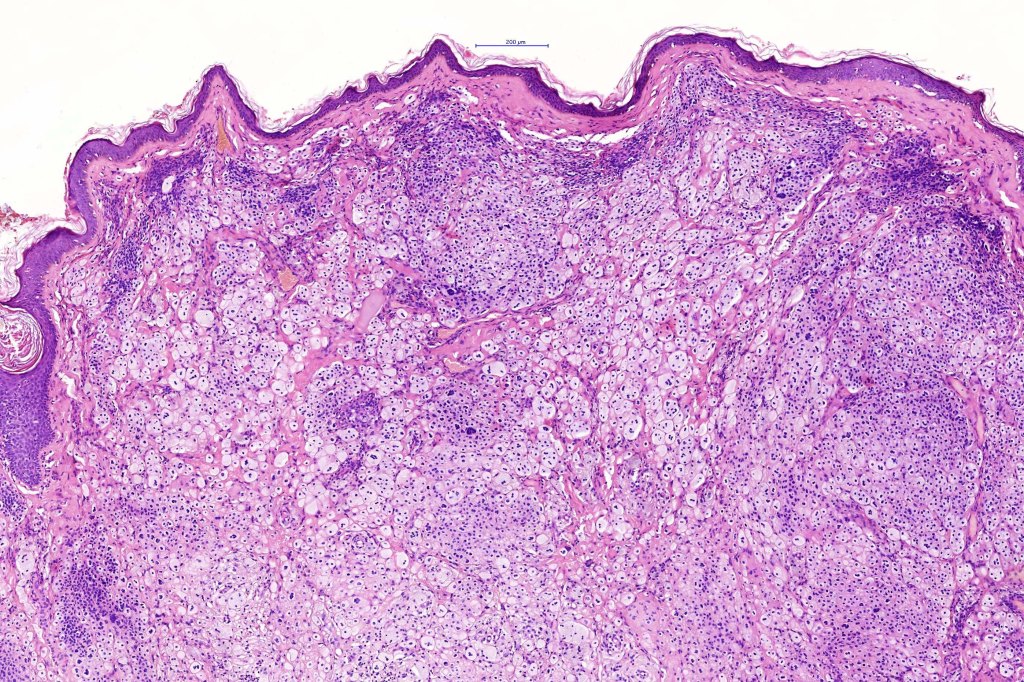

Histological features

.Balloon cell change is most often seen in banal melanocytic nevi but it has also rarely been described in cellular blue nevus, dysplastic nevus, combined nevus, halo nevus & Spitz nevus. Lesions with <50% of balloon cells are sometimes described as nevi with balloon cells. Nevi with >50% balloon cells are described as balloon cell nevus.

.Balloon cell nevs genrally has uniform, hyperchromatic nuceli (as opposed to the vesicular nuclei with prominent nucleoli) seen in melanoma. Mitoses are absent.(In my experience, balloon cell melanoma is more common than balloon cell nevus).

. In some balloon cell nevi, the microvesicles may result in nuclear scalloping reminiscent of a sebaceous tumor. In cases where there is real doubt, immunohistochemistry (S100), SOX10) will resolve the problem.

The importance of the entity is that it must always be distinguished from balloon cell melanoma. All cases should be scrutinized very carefully for pleomorphism and mitotic activiy before rendering a diagnosis of balloon cell nevus.